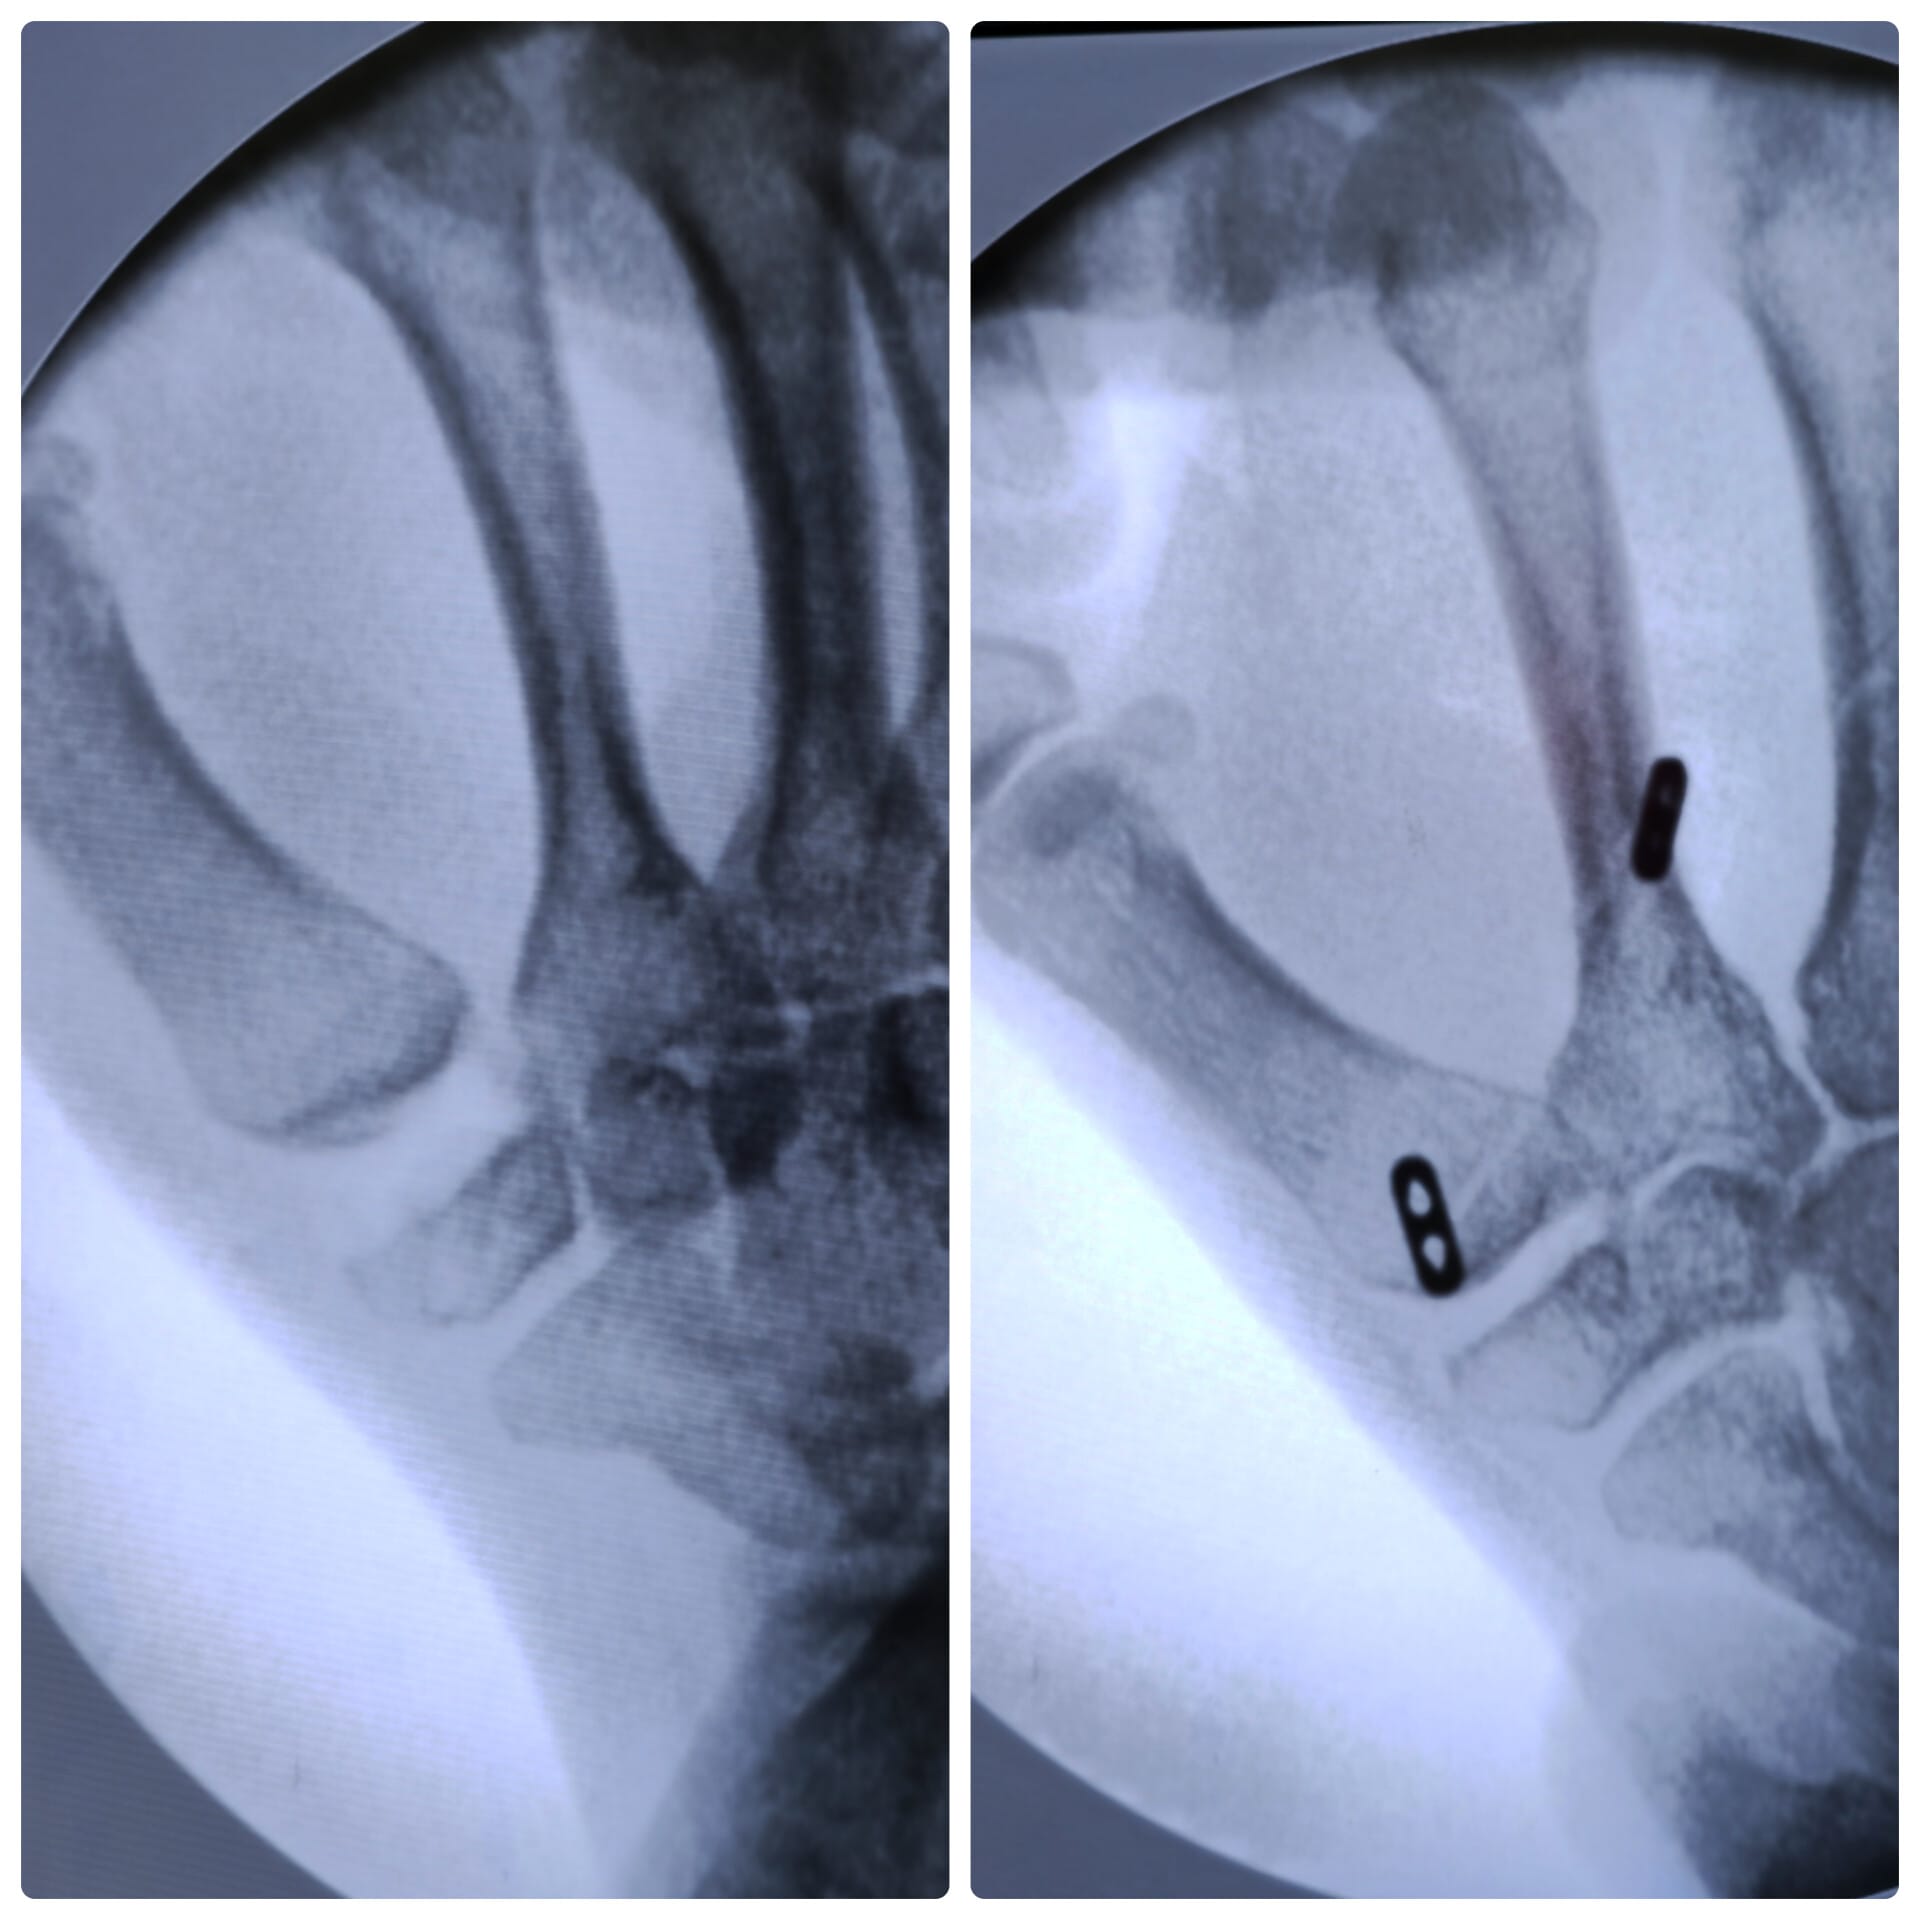

La artroscopia se realiza introduciendo una pequeña cámara (una “óptica”) dentro de la muñeca. Esa cámara nos muestra en una pantalla todo lo que ocurre dentro de la articulación: cartílago, ligamentos, el fibrocartílago triangular (FCT) y cualquier zona dañada.

A través de otros orificios milimétricos se introducen instrumentos finos que permiten reparar, limpiar o tratar la lesión.

Evaluación y tratamiento de fracturas de radio distal o fracturas dentro de la articulación.